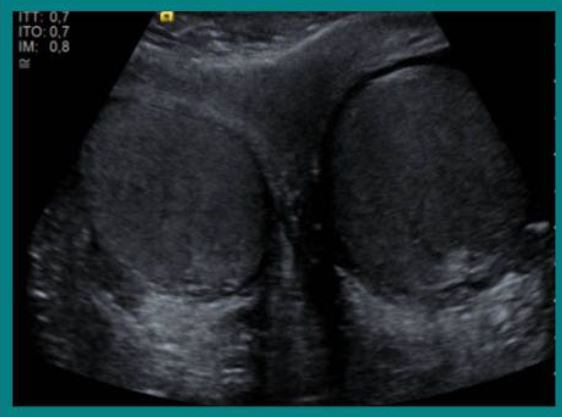

La ecografía constituye el método ideal para el estudio de la patología escrotal, adquiriendo un papel fundamental en el diagnóstico y seguimiento de los tumores testiculares, dado que alcanza una sensibilidad próxima al 100% en su detección.

El objetivo de este trabajo es hacer una revisión del cáncer testicular y los hallazgos radiológicos, fundamentalmente ecográficos, de los distintos tumores y su correlación con el tipo histológico.

El cáncer testicular representa un 1% de las neoplasias en varones, sin embargo constituye la enfermedad maligna más frecuente en el grupo comprendido entre 15 y 34 años de edad. Se presenta en la mayoría de los casos como una masa escrotal indolora o un aumento indoloro del tamaño testicular (Figura 1).